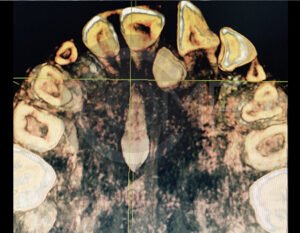

Antes de la extracción se realiza una valoración clínica y estudios de imagen, como radiografías panorámicas o tomografías, para conocer la posición del tercer molar, su relación con los nervios y planificar un procedimiento seguro y adecuado para cada paciente.

No es recomendable. Antes de extraer terceros molares es necesario realizar una valoración clínica y estudios de imagen para conocer la posición del diente, su relación con los nervios y el tipo de procedimiento más seguro para cada paciente.

Algunas extracciones simples de otras piezas dentales pueden ser realizadas por un odontólogo general; sin embargo, por la complejidad que presentan los terceros molares, o si se encuentran retenidos, impactados o cerca de estructuras importantes, se recomienda que el procedimiento sea realizado por un cirujano maxilofacial para mayor seguridad y control del tratamiento.